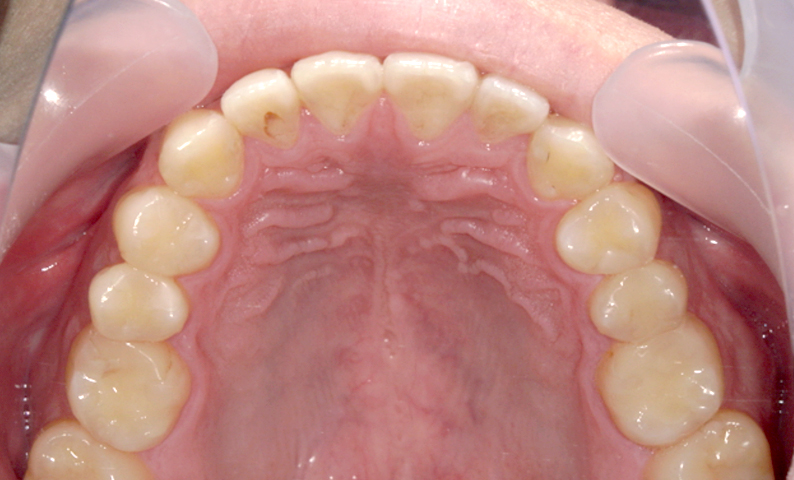

| 治療前 | 治療後 |

|---|---|

|